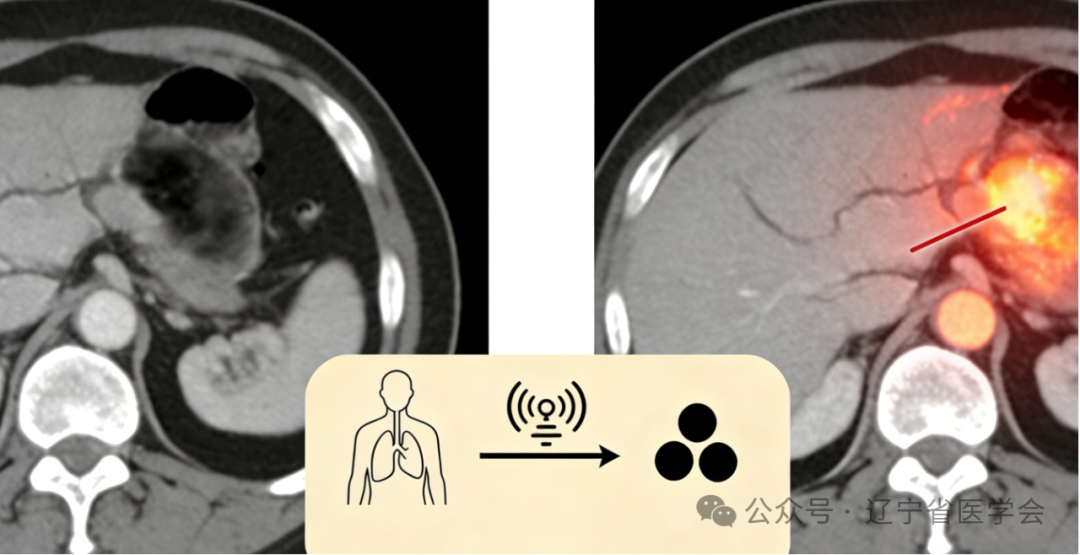

原理: 碘能强烈地吸收X射线。当造影剂到达血管丰富或血流异常的组织(如肿瘤、炎症、血管病变区域)时,该区域在CT图像上就会比周围正常组织显得更“亮”(密度增高)。反之,血供差的区域则显得相对“暗”。这种鲜明的对比,让医生能清晰分辨病变的位置、大小、形态、血供情况以及与周围组织的关系。

1.发现隐藏病灶:尤其是血供丰富的肿瘤、小血管畸形、早期炎症等,平扫可能漏诊,增强后则“原形毕露”。

2.明确病变性质:不同性质的病变(良/恶性肿瘤、脓肿、血管瘤等)在增强后呈现不同的强化模式(快进快出、慢进慢出、环形强化等),帮助医生判断。